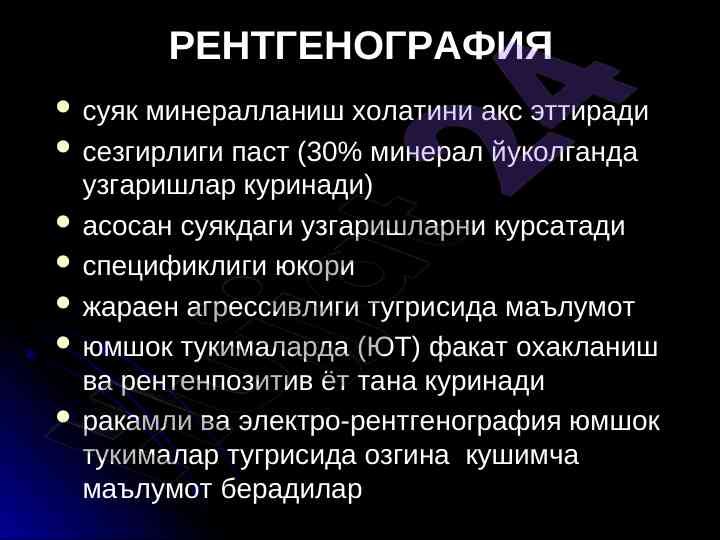

Рентгенография, ультрасонография ва сцинтиграфия усуллари тянч-харакат тизими касалликлари диагностикасида муhim аҳамиятга эга. Инсон организмининг юз бериши мумкин бўлган ўзгаришларни аниқлашда муҳим рол ўйнайди.